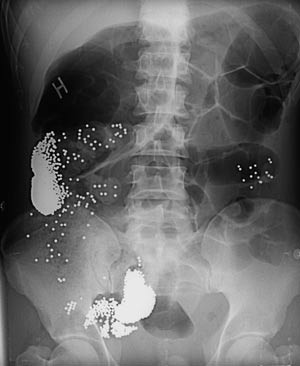

På grunn av magesmerter ble det tatt røntgen oversikt abdomen, som viste to større ansamlinger av metalltette partikler. I tillegg var det metallpartikler spredt i hele abdomen (fig 2). Partiklene var forenlig med blyhagl nr. 7, og det ble anslått at det var ca. 120 g til sammen. Dette tilsvarer omtrent innholdet i fire haglpatroner. Pasienten benektet imidlertid annet mulig inntak av hagl enn at han hadde spist hare- og selkjøtt flere måneder før innleggelsen. Komparenter fortalte at det var funnet flere tomme haglpatronhylser hjemme hos pasienten.